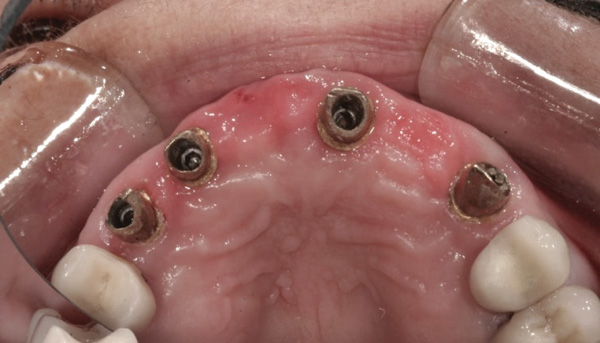

Case 3 – Remilling of Custom Abutments

Background: In this case, the patient had a failing mandibular and maxillary dentition due to caries secondary to radiation-induced xerostomia. The patient had had a radical neck dissection to remove a squamous cell carcinoma of the throat 9 years prior to his prosthodontic consultation with the authors. The patient reported a history of radiation therapy following surgery, but did not have a shielding stent. A staged approach was used so as to avoid removable prosthetics on his severely dry soft tissues. He chose to treat his mandibular issues first. Figure 9 shows healing abutments next to the temporarily retained natural teeth, and Figure 10 shows the first-stage custom abutments inserted with relatively good gingival contour and no recession. Recession was clearly seen around all first-stage abutments following adjacent extractions and second-stage implant placement (Figure 11).

Results: The decision was made to remove these abutments and make a fixture-level impression of all the implants so that both new and first-stage abutments could be milled together for parallelism and proper gingival margin location. Because this requires the removal of the first-stage abutments that were retaining the provisional prosthesis, temporary abutments were placed prior to removal of all custom abutments in order to assure proper seating and vertical dimension of the provisional. These temporary abutments then retained the provisional while all custom abutments were fabricated and/or milled in the laboratory. Figure 12 shows the placement of the remilled (first-stage implants) and new (second-stage implants) custom abutments.

Figure 12 Remilled and new custom abutments.

Figure 12